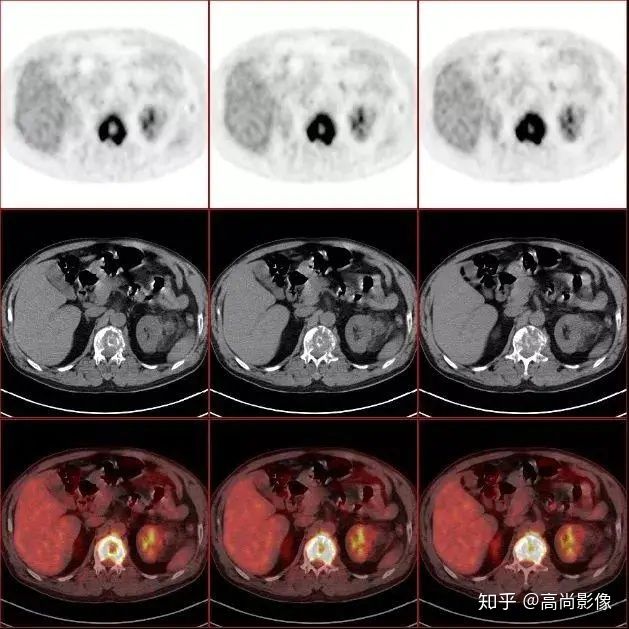

(胸椎骨轉(zhuǎn)移合并病理性骨折)

(右側(cè)髖臼骨轉(zhuǎn)移)